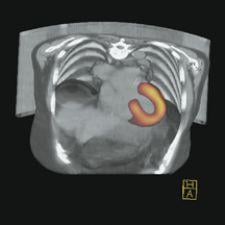

The Precedence SPECT/CT system from Philips Medical Systems

Philips Medical Systems and Siemens Medical Solutions are two of the leading manufacturers of multislice SPECT/CT systems. Philips offers the Precedence 6-, 16-, and 64-slice SPECT/CT systems and Siemens offers the 2- and 6-slice Symbia TruePoint SPECT/CT.

Philips debuted the 64-slice Precedence SPECT/CT at the American Society of Nuclear Cardiology (ASNC) in Montreal, Canada in September 2006. The 64-slice Precedence SPECT/CT is the first system to offer 64-slice CT capabilities, and has the benefit of being a full 64-slice diagnostic CT system, a full diagnostic SPECT system and a combination hybrid.

“The Precedence 64 is the only device that can do myocardial perfusion imaging with attenuation correction, calcium scoring and coronary CTA all on the same device in one episode of care,” said Liebig.